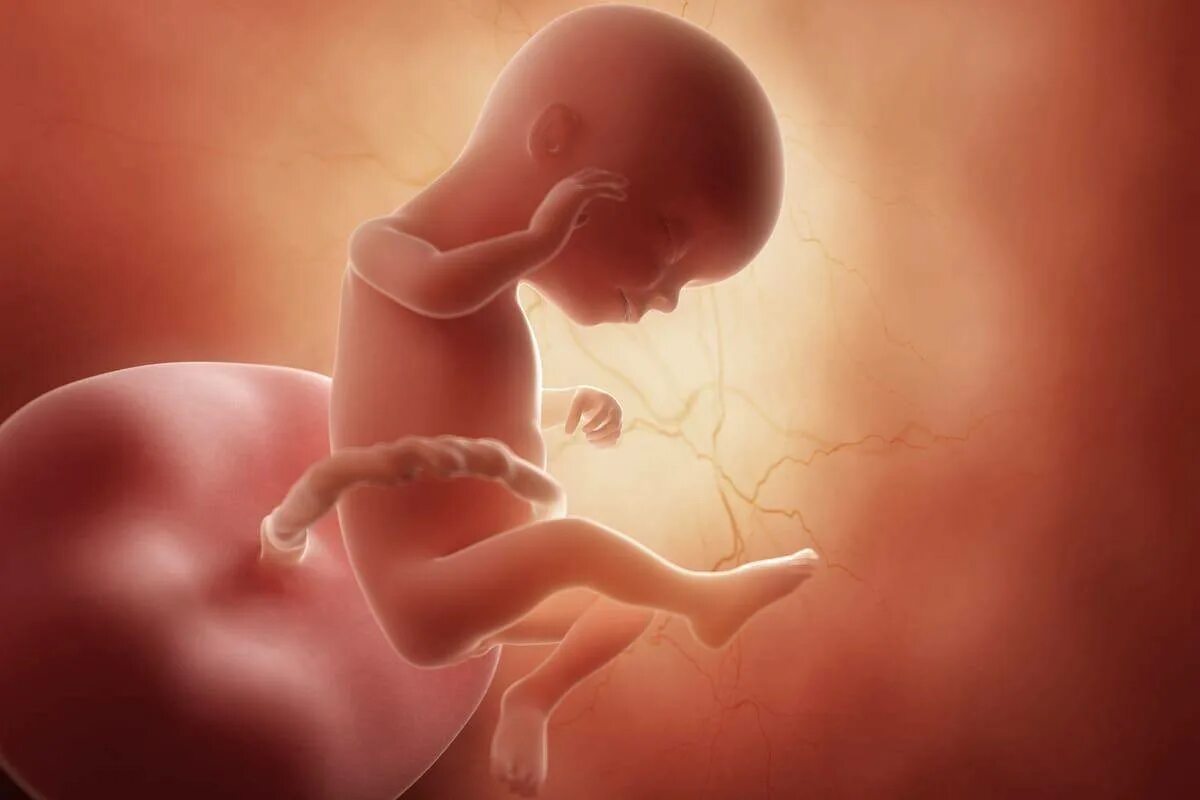

Как выглядит ребенок в 18 недель